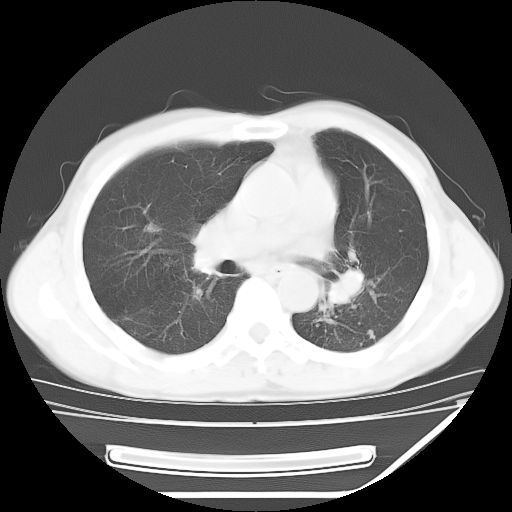

男,59岁,“结核性胸膜炎”30余年,胸部经常疼痛,多次x检查提示“肺部”炎症。腹部疼痛5日,b超提示:“肝内短管结石,余显示不清,建议进一步检查。”

两肺结核并右侧胸腔积液;脾脏、腹腔及腹膜后淋巴结结核[陈旧性];肝内胆管结石

胸部腹部都是结核(双肺。纵隔淋巴结,肝脏,脾脏,肠系膜)

两肺结核并右侧胸腔积液;脾脏、腹腔及腹膜后淋巴结结核[陈旧性];肝内胆管结石。直肠息肉?